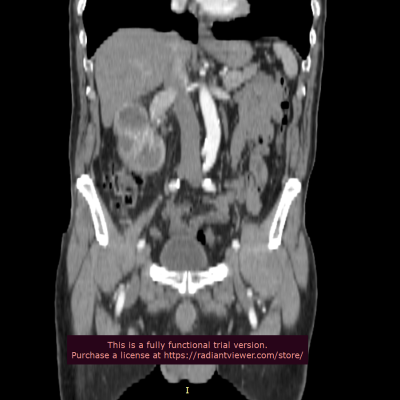

Права нирка типового положення, деформована за рахунок наявної неопластичної інфільтрації в передньо-латеральних відділах паренхіми середньо-нижнього сегментів з формуванням вузлового компоненту, що частково виходить за межі та деформує поверхню розміром 55*45 мм, структура гетерогенна з нерівномірним накопиченням контрасту, чітке відмежування від паренхіми – відсутнє. Нерівномірно сегментарно обтурован просвіт миски за рахунок інфільтрації на всьому протязі до рівня мисково-сечовідного сегменту.

Артерія – типового ретрокавального положення, без ознак обтурації просвіту, з наявною паравазальною інфільтрацією практично до рівня основи, інтактний відрізок до 17 мм від стінки аорти. Вена – шириною 25 мм, своєчасно контрастована, в ділянці воріт – втягнута в процес ураження, позаду та нижче на 11 мм від основної гілки від нижньої полої вени відходить гілка шириною до 3 мм, що васкуляризує нижній сегмент.

Висновок СКТ: Cr renis dextrae з тотальною інфільтрацією стінок миски, сформованим вузловим компонентом в передніх відділах середнього сегменту, інфільтрація поширюється вздовж стінок ренальної артерії, субтотально.